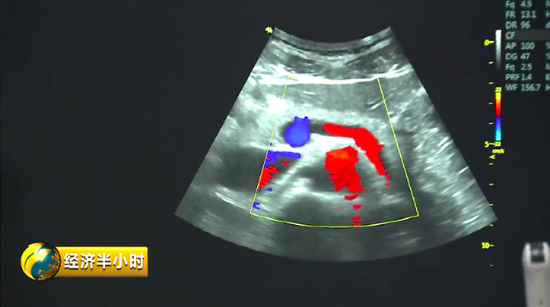

“彩超”,人们并不陌生,但是既能诊断又能帮助治疗的“彩超”对大多数人来说却是陌生的。

有一个特殊的彩色B超设备,不仅能够精确诊断,还能帮助大夫有效地给予患者治疗。也就是说,在治疗疾病时,在超声波的介入下,药物被精准送达病变位置,释放药物,从而实现靶向治疗。而且这个彩色B超设备副作用很少,安全性特别好。《经济半小时》记者在苏州工业园区了解到,目前这种彩色B超设备在国际上已经达到一流水平。

显示速率越快,意味着成像效果越好,医生的诊断和治疗也会更精确。公司研发总监高文友告诉记者,他们一代数据处理平台的速度可以理解成 5G 速度的 10 倍,而目前开发出来的二代产品,传输带宽比上一代高了将近150倍;成像显示的速率,也将近快了一百倍以上。

2014年,公司靠着自主创新,终于研制出具有完全知识产权、性能达到世界一流水平的彩色B超设备。

彩色B超设备